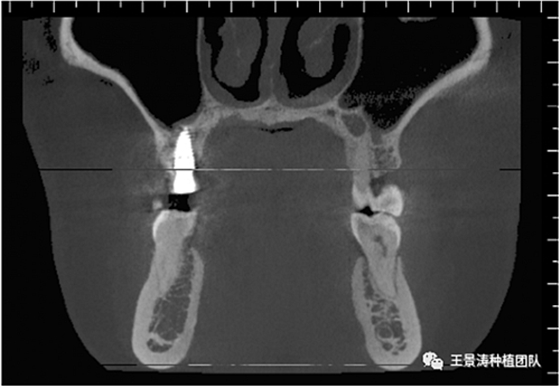

下述病例則是15區(qū)域的即刻種植,15因牙冠折斷于齦下,無法樁核冠修復(fù),則考慮種植修復(fù)。但拍攝CBCT后發(fā)現(xiàn)根尖距上頜竇底距離較短。患者為年輕女性,無全身系統(tǒng)疾病且可利用上頜竇底與根尖皮質(zhì)骨雙側(cè)皮質(zhì)骨固位,且此位置可通過頰側(cè)軟組織減張技術(shù)獲得嚴(yán)密封閉牙槽窩。因其根尖距上頜竇距離較低,遂拔除15后行上頜竇內(nèi)提升,埋入式種植,最終修復(fù)的完成。

左側(cè)下頜第二磨牙及右側(cè)下頜第一磨牙同時(shí)即刻種植病例?;颊吣贻p女性,無系統(tǒng)性疾病。37及46殘冠及殘根,且46劈裂,無法冠修復(fù),必須拔除。37根尖慢性炎癥,大量肉芽組織存在,46根分叉較高,根分叉骨質(zhì)尚可。CBCT示:根尖骨質(zhì)至下牙槽神經(jīng)管距離可滿足種植體的初期穩(wěn)定性,遂考慮即刻種植,并在種植體周邊填入骨粉并覆蓋骨膜,雙側(cè)的種植體初期穩(wěn)定性相差無幾,但考慮到37根尖慢性炎癥較大,遂給予埋入式種植。